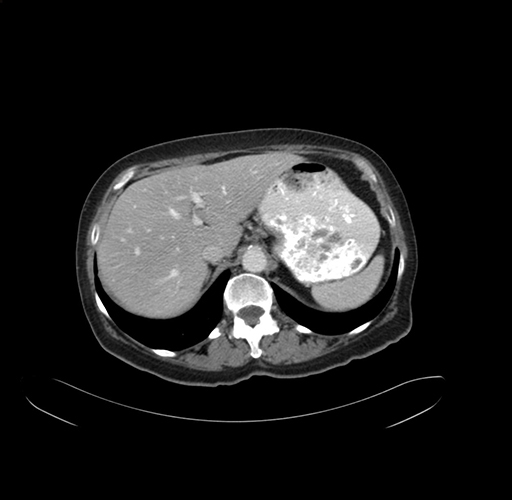

Pre-Chemo: Axial Venous

Axial Venous

Imaging analysis

Based on your CT findings, which issue(s) would give reason for "planned slowing down moment(s)" in this case?

Considering a standard right hepatectomy procedure, what step(s) of the operation would you do differently in this case?